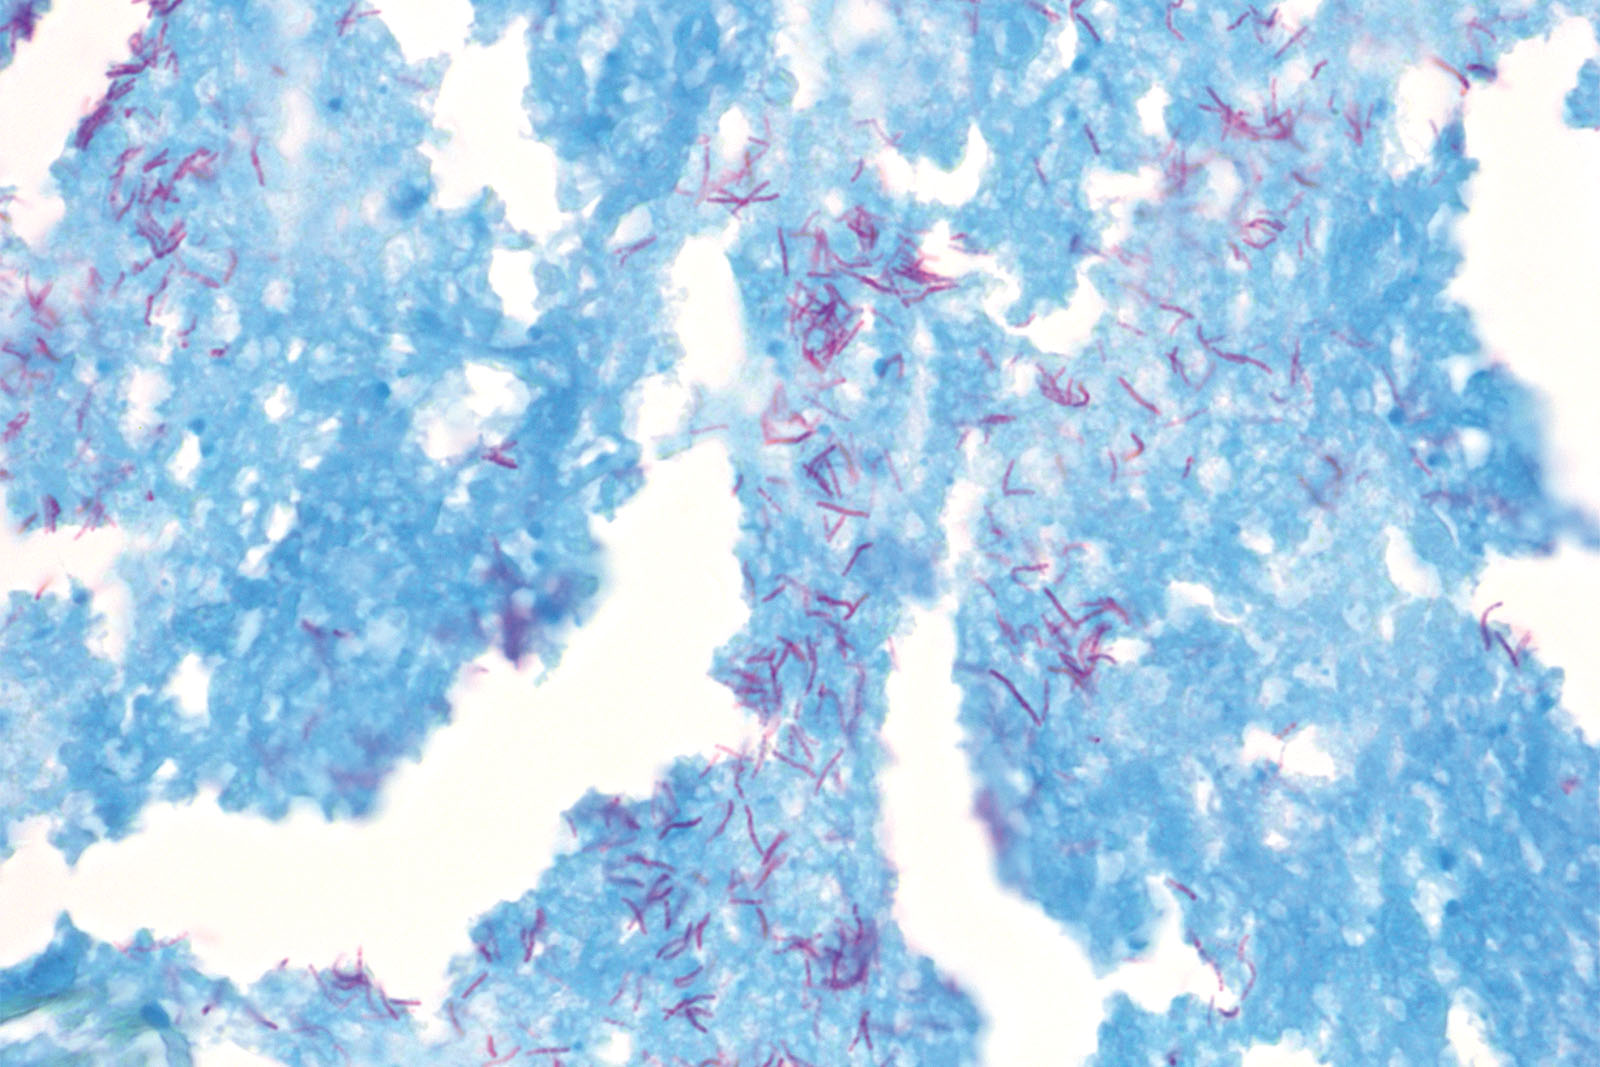

Many bacterial cells are easily stained by using simple dyes or Gram stain. However, a few bacterial strains, such as Mycobacteria and Nocardia cannot be stained using simple dyes (or, if successfully stained, the results may vary significantly). Cellular wall of the Mycobacteria strain contains a waxy substance – mycolic acid. Those are beta-hydroxy carboxylic acids with chains containing up to 90 carbon atoms. Its resistance to acidity is associated with mycolic acid chain length. In order to stain such strains, a higher concentration of dye or a longer period of heating is required. However, once stained, the dye is even more difficult to remove from the cells. Those bacteria are called acid-resistant because they maintain their primary color even after decolorization using acid alcohol (Carbol Fuchsin). Early laboratory diagnosis of tuberculosis is based on the interpretation of stained smears, and one of the best diagnostic methods is analyzing sputum samples under a microscope. The most common and renowned method used for detecting the tuberculosis bacteria is staining according to Ziehl-Neelsen. This method uses Carbol Fuchsin as the main dye, acid alcohol as decolorization medium and Methylene Blue solution as a contrasting dye. BioGnost’s TB-Stain Hot kit contains TB Carbol Fuchsin reagent, two packages of TB Decolorizer and Methylene Blue Loeffler reagent.